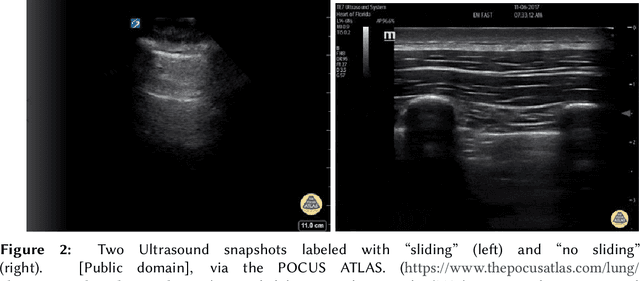

Abstract:Point-of-Care Ultrasound (POCUS) refers to clinician-performed and interpreted ultrasonography at the patient's bedside. Interpreting these images requires a high level of expertise, which may not be available during emergencies. In this paper, we support POCUS by developing classifiers that can aid medical professionals by diagnosing whether or not a patient has pneumothorax. We decomposed the task into multiple steps, using YOLOv4 to extract relevant regions of the video and a 3D sparse coding model to represent video features. Given the difficulty in acquiring positive training videos, we trained a small-data classifier with a maximum of 15 positive and 32 negative examples. To counteract this limitation, we leveraged subject matter expert (SME) knowledge to limit the hypothesis space, thus reducing the cost of data collection. We present results using two lung ultrasound datasets and demonstrate that our model is capable of achieving performance on par with SMEs in pneumothorax identification. We then developed an iOS application that runs our full system in less than 4 seconds on an iPad Pro, and less than 8 seconds on an iPhone 13 Pro, labeling key regions in the lung sonogram to provide interpretable diagnoses.

Abstract:Computer-aided diagnosis for medical imaging is a well-studied field that aims to provide real-time decision support systems for physicians. These systems attempt to detect and diagnose a plethora of medical conditions across a variety of image diagnostic technologies including ultrasound, x-ray, MRI, and CT. When designing AI models for these systems, we are often limited by little training data, and for rare medical conditions, positive examples are difficult to obtain. These issues often cause models to perform poorly, so we needed a way to design an AI model in light of these limitations. Thus, our approach was to incorporate expert domain knowledge into the design of an AI model. We conducted two qualitative think-aloud studies with doctors trained in the interpretation of lung ultrasound diagnosis to extract relevant domain knowledge for the condition Pneumothorax. We extracted knowledge of key features and procedures used to make a diagnosis. With this knowledge, we employed knowledge engineering concepts to make recommendations for an AI model design to automatically diagnose Pneumothorax.